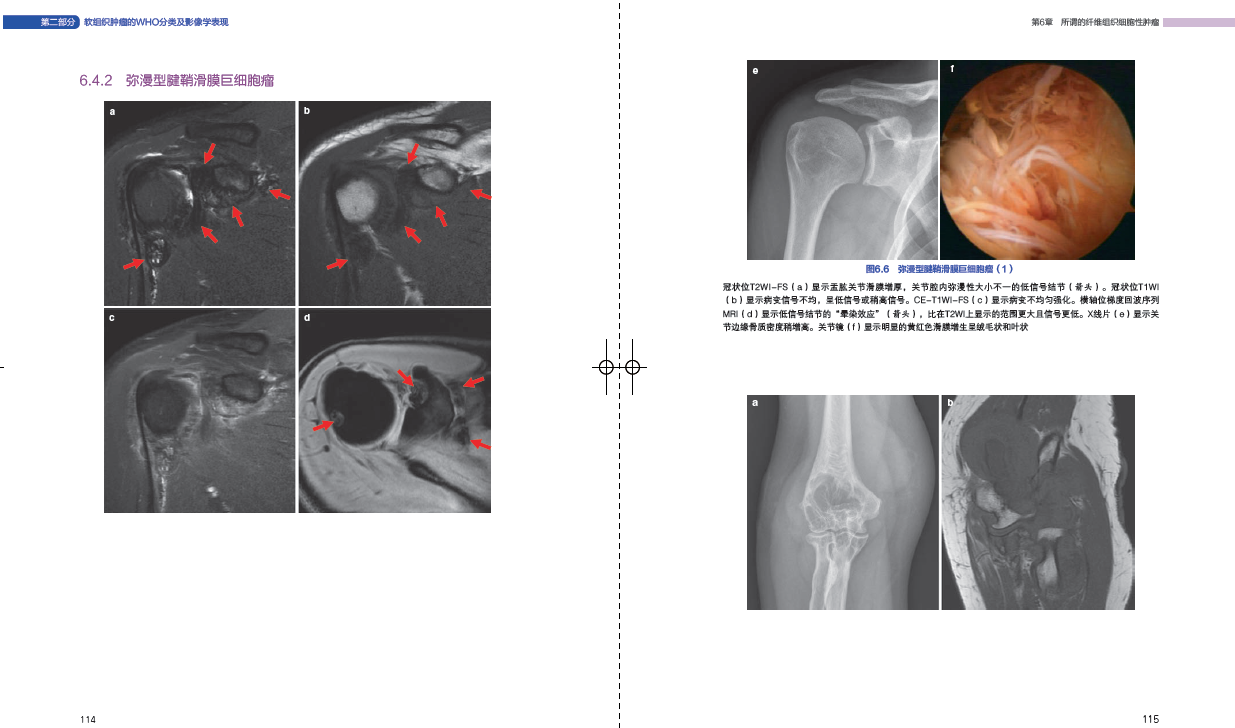

第6章 所谓的纤维组织细胞性肿瘤108

61 腱鞘滑膜巨细胞瘤108

64 示例:所谓的纤维组织细胞性肿瘤110